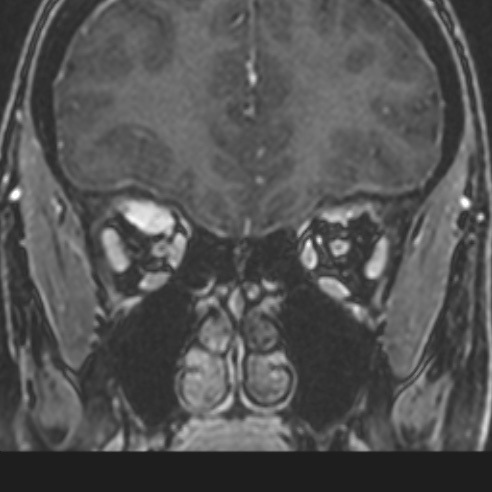

CT scans reveal calcification along the optic nerve in a “tram-track” configuration which occurs in 20-30% of patients with NF type II.